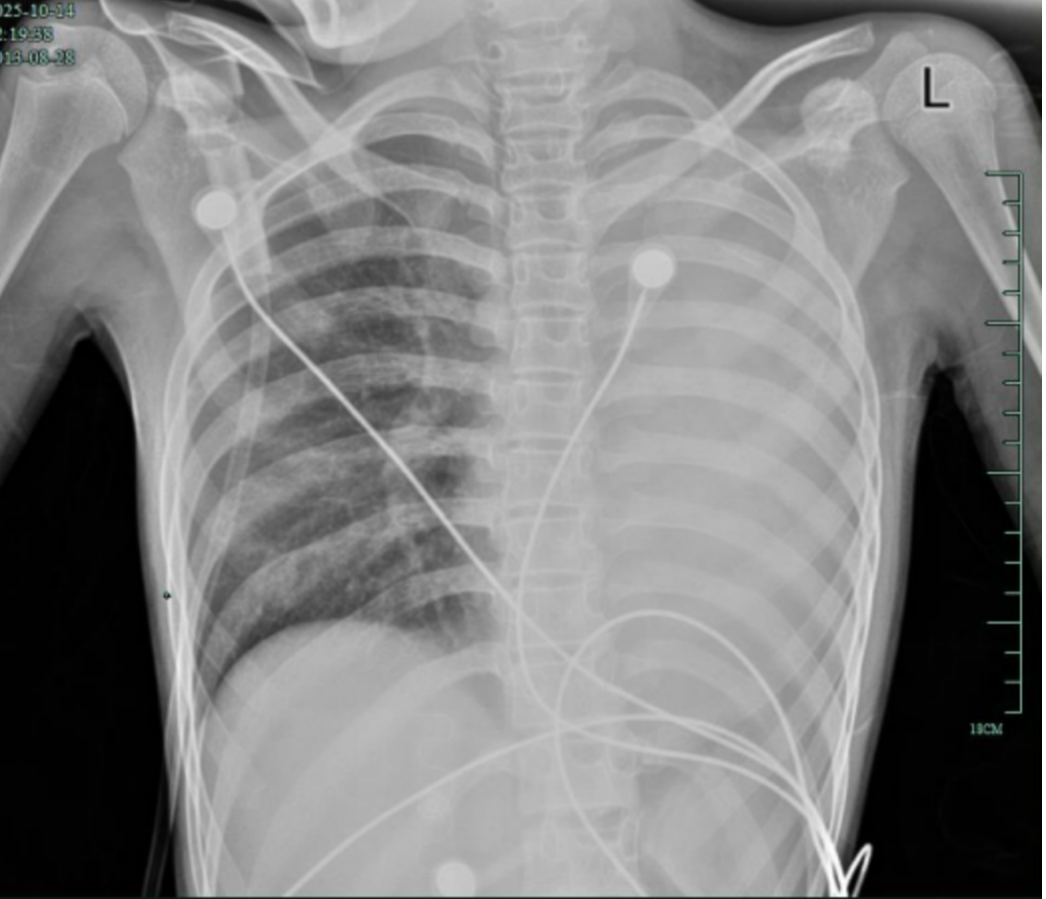

入院后,笑笑很快出现呼吸急促、胸闷胸痛,只能靠面罩吸氧维持血氧,胸片显示左肺已完全呈“白肺”改变,肺部炎症进展迅猛。

(治疗前,左肺呈“白肺”状态)